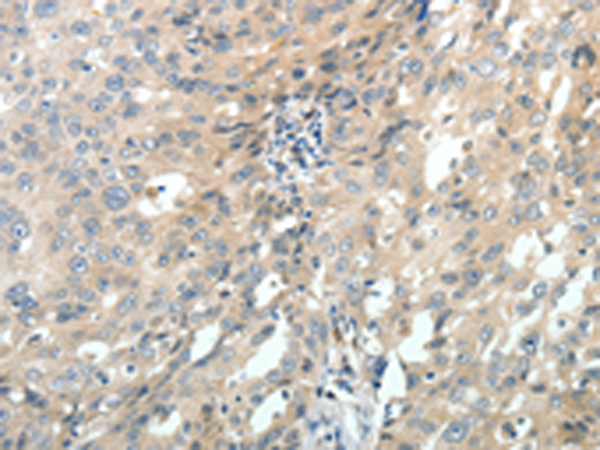

分类: 科研抗体货号: P04273别名: C9; DD1; DDH; DDH1; H-37; HBAB; MBAB; HAKRC; DD1/DD2; 2-ALPHA-HSD; 20-ALPHA-HSD应用: WB,IHC反应种属: Human